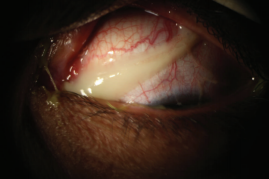

图1. 菌性结膜炎患者的眼部出现浓稠的分泌物